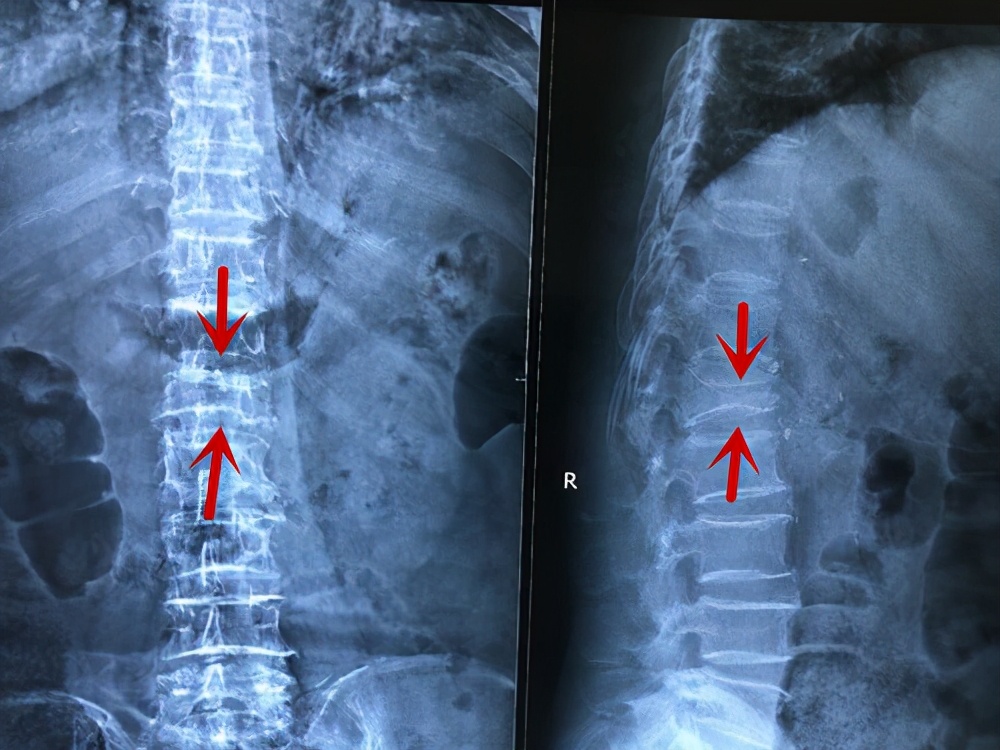

首先是要确诊,X线可以作为初步的检查,判断椎体是否有压缩性改变。

而核磁共振可以明确是否是新发生(新鲜)的骨折,因为陈旧的压缩性骨折在X线片上也是压缩性改变。